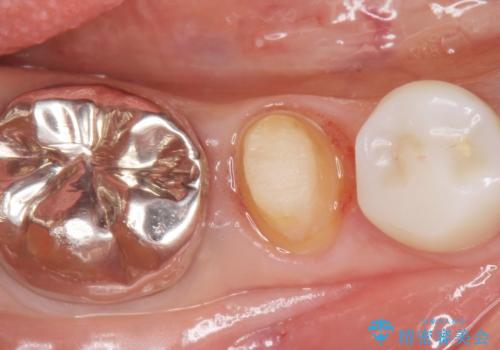

精査したところ、被せ物を入れたばかりの右下の小臼歯(右下5)は不可逆性歯髄炎により神経をとる処置(抜髄)が必要な状態でした。

根管治療後、セラミッククラウンによる補綴治療を行いました。